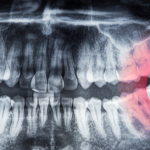

Oral health and heart health

Did you know that gum disease can also be bad news for your ticker? According to the Heart Foundation, people with gum disease are twice as likely to have heart disease. And that’s a big deal. Heart disease was the number one cause of all deaths in Australia for the 2021 reference period.

Scientists have established a link between oral health and heart disease. However, they’re quick to point out that more research is needed to establish a direct cause between the two. Current theories suggest the bacteria from infected gums travel to the heart. This bacteria transfer can then result in endocarditis, an infection of your heart lining.

Another theory is our body’s response (immunity) to gum bacteria in the heart can cause inflammation, clots, or sticky blood vessels. This results in cholesterol collection, which then leads to decreased or blocked blood flow.